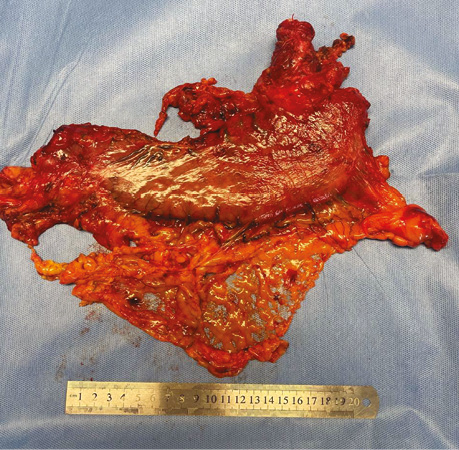

Обстеження та планування лікування. Лабораторні показники без клінічно значущих відхилень. Радіологічні дані, комп’ютерна томографія органів підтвердили наявність потовщення стінок нижньої третини стравоходу та кардіального відділу шлунка до 31 мм (рис. 1).

Рис. 1. Радіологічні дані локалізації первинної пухлини